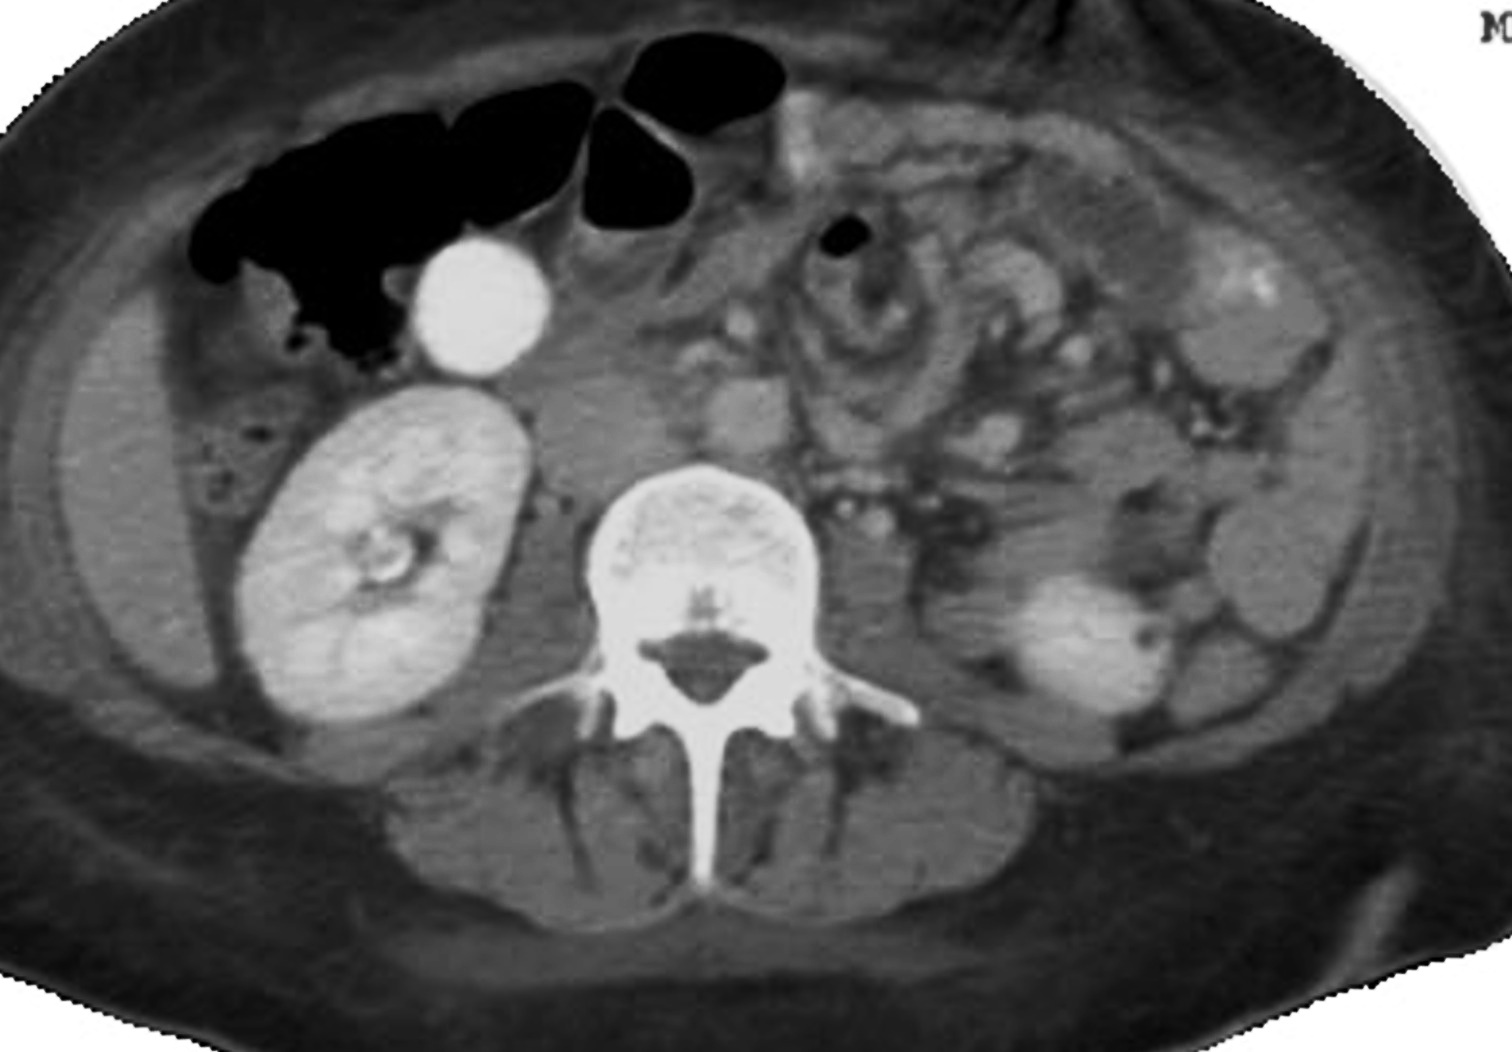

More on the CT whirl sign of volvulus

Attached are some more views of the whirl as well as autopsy photos of the twisted intestine-mesintary. This whirl appears to be a particularly tight one. A fact confirmed by the autopsy photos. The patient survived a day and three quarters post CT.